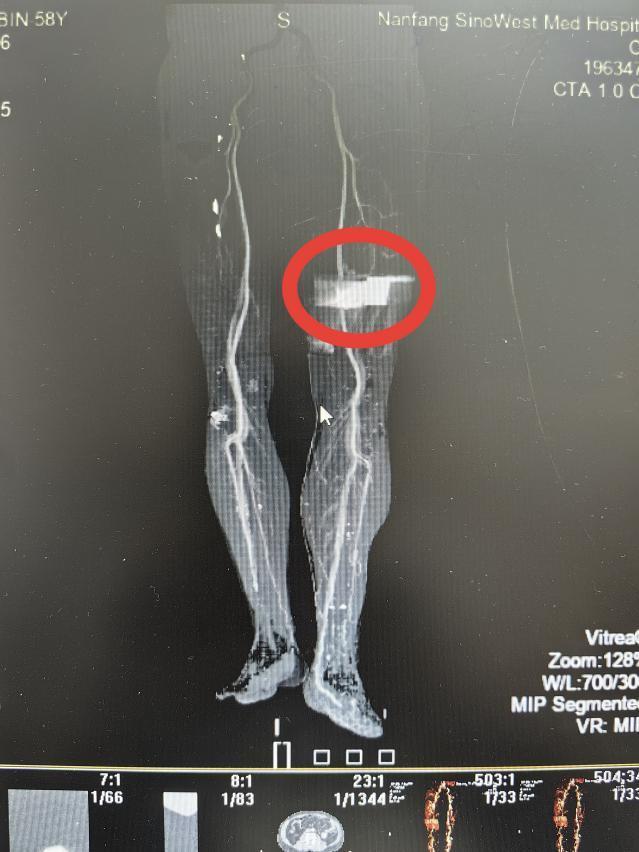

张先生被紧急送至该院急诊室。三维血管造影检查显示,金属异物位置极为凶险:其穿行路径紧邻人体主要动脉之一的股动脉。异物与股动脉间距极小,一旦损伤该血管,将导致快速致命性大出血,需紧急处置。

徐楚江带领团队进行了精细的手术操作。术中发现金属异物与股动脉、股静脉紧密粘连,距离坐骨神经仅几毫米距离。手术需要极高的操作精度,稍有不慎就可能损伤重要血管或神经,引发大出血或永久性神经功能损伤,严重时会导致下肢瘫痪。经过一个多小时的谨慎操作,医护团队成功将异物与周围血管、神经分离,完整取出金属异物。